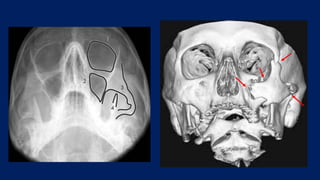

• CT- Facial bones – gold standard

• 3D CT – normal vs abnormal rim and malar eminence

DIAGNOSIS • History • Clinicalexamination • X-ray Water’s view - Zygoma buttresses, orbital floor, inf. orbital rim, ZF suture, ZM buttress Caldwell view – ZF suture • CT- Facial bones – gold standard • 3D CT – normal vs abnormal rim and malar eminence